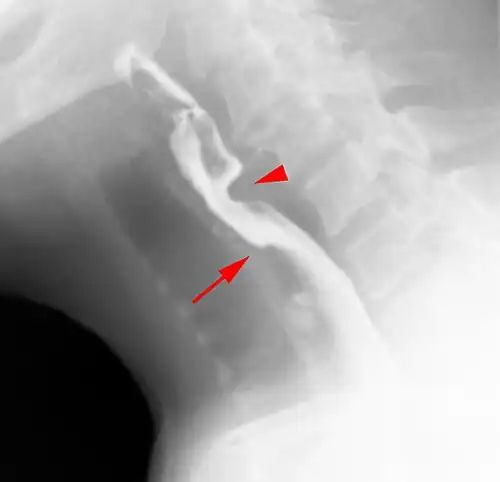

Web with "jet-phenomenon". Arrowhead on incomplete opening of the upper esophageal sphincter. -

The diagnostic test of choice is a barium swallow.